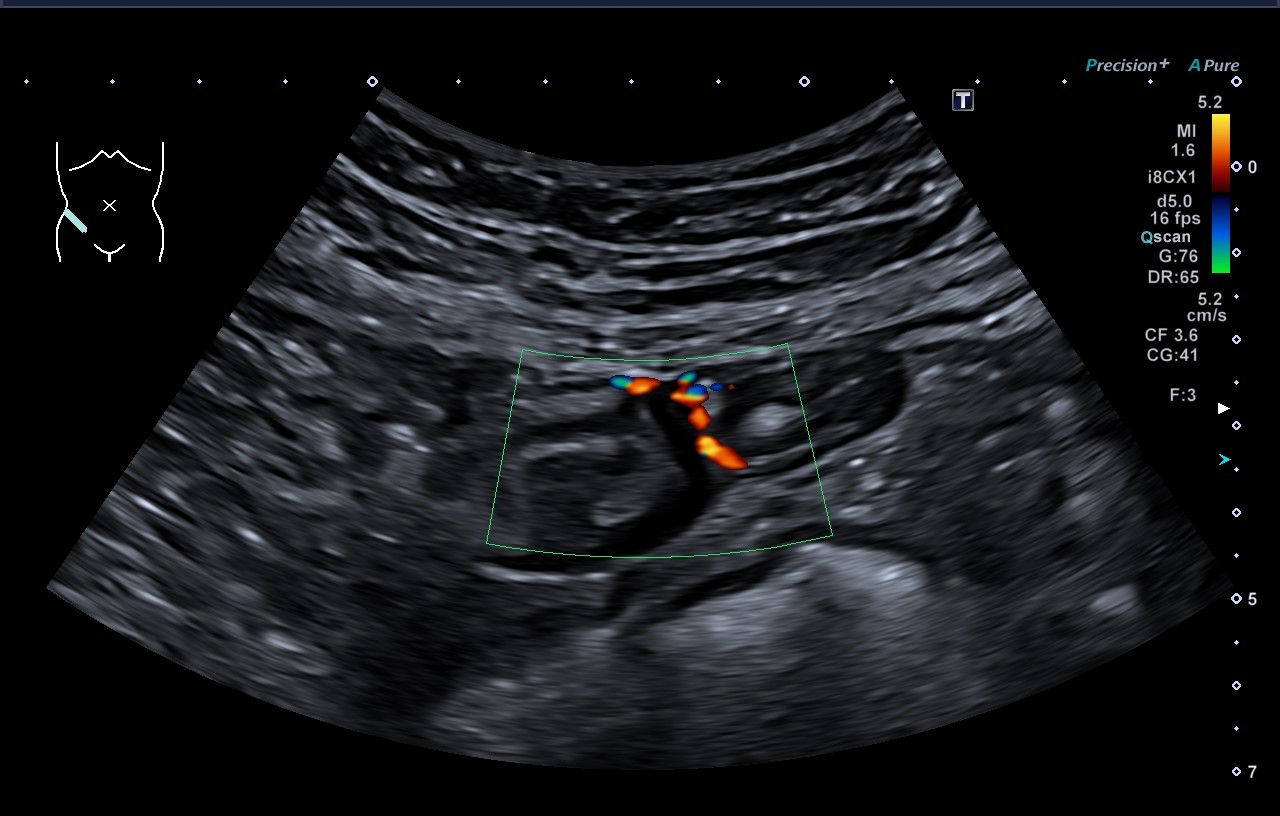

Ecografía abdominal: Con esta técnica podemos evaluar diferentes órganos intraabdominales: hígado, bazo, vesícula biliar, páncreas, riñones, vejiga y grandes vasos abdominales. Desde hace varios años disponemos de contrastes ecográficos intravenosos que nos ayudan a mejorar la caracterización de ciertas lesiones a nivel hepático, vía biliar, vasculares, entre otras. Su seguridad, ausencia de hepato o nefrotoxicidad nos permiten administrarlos en algunos pacientes con ciertas patologías, que de otra forma no podrían recibir otro tipo de contrastes.

Biopsia hepática, punciones de tumores (LOEs): a través de la ecografía podemos orientar o guiar las punciones hepáticas. Esto nos permite recoger una muestra de tejido, lo cual es muy útil para ayudar a diagnosticar distintos tipos de enfermedades del Hígado. Igualmente podemos tomar muestras de lesiones o tumores, que se encuentren en el hígado, cercanos al mismo o que sean accesibles por vía abdominal (transparietal).